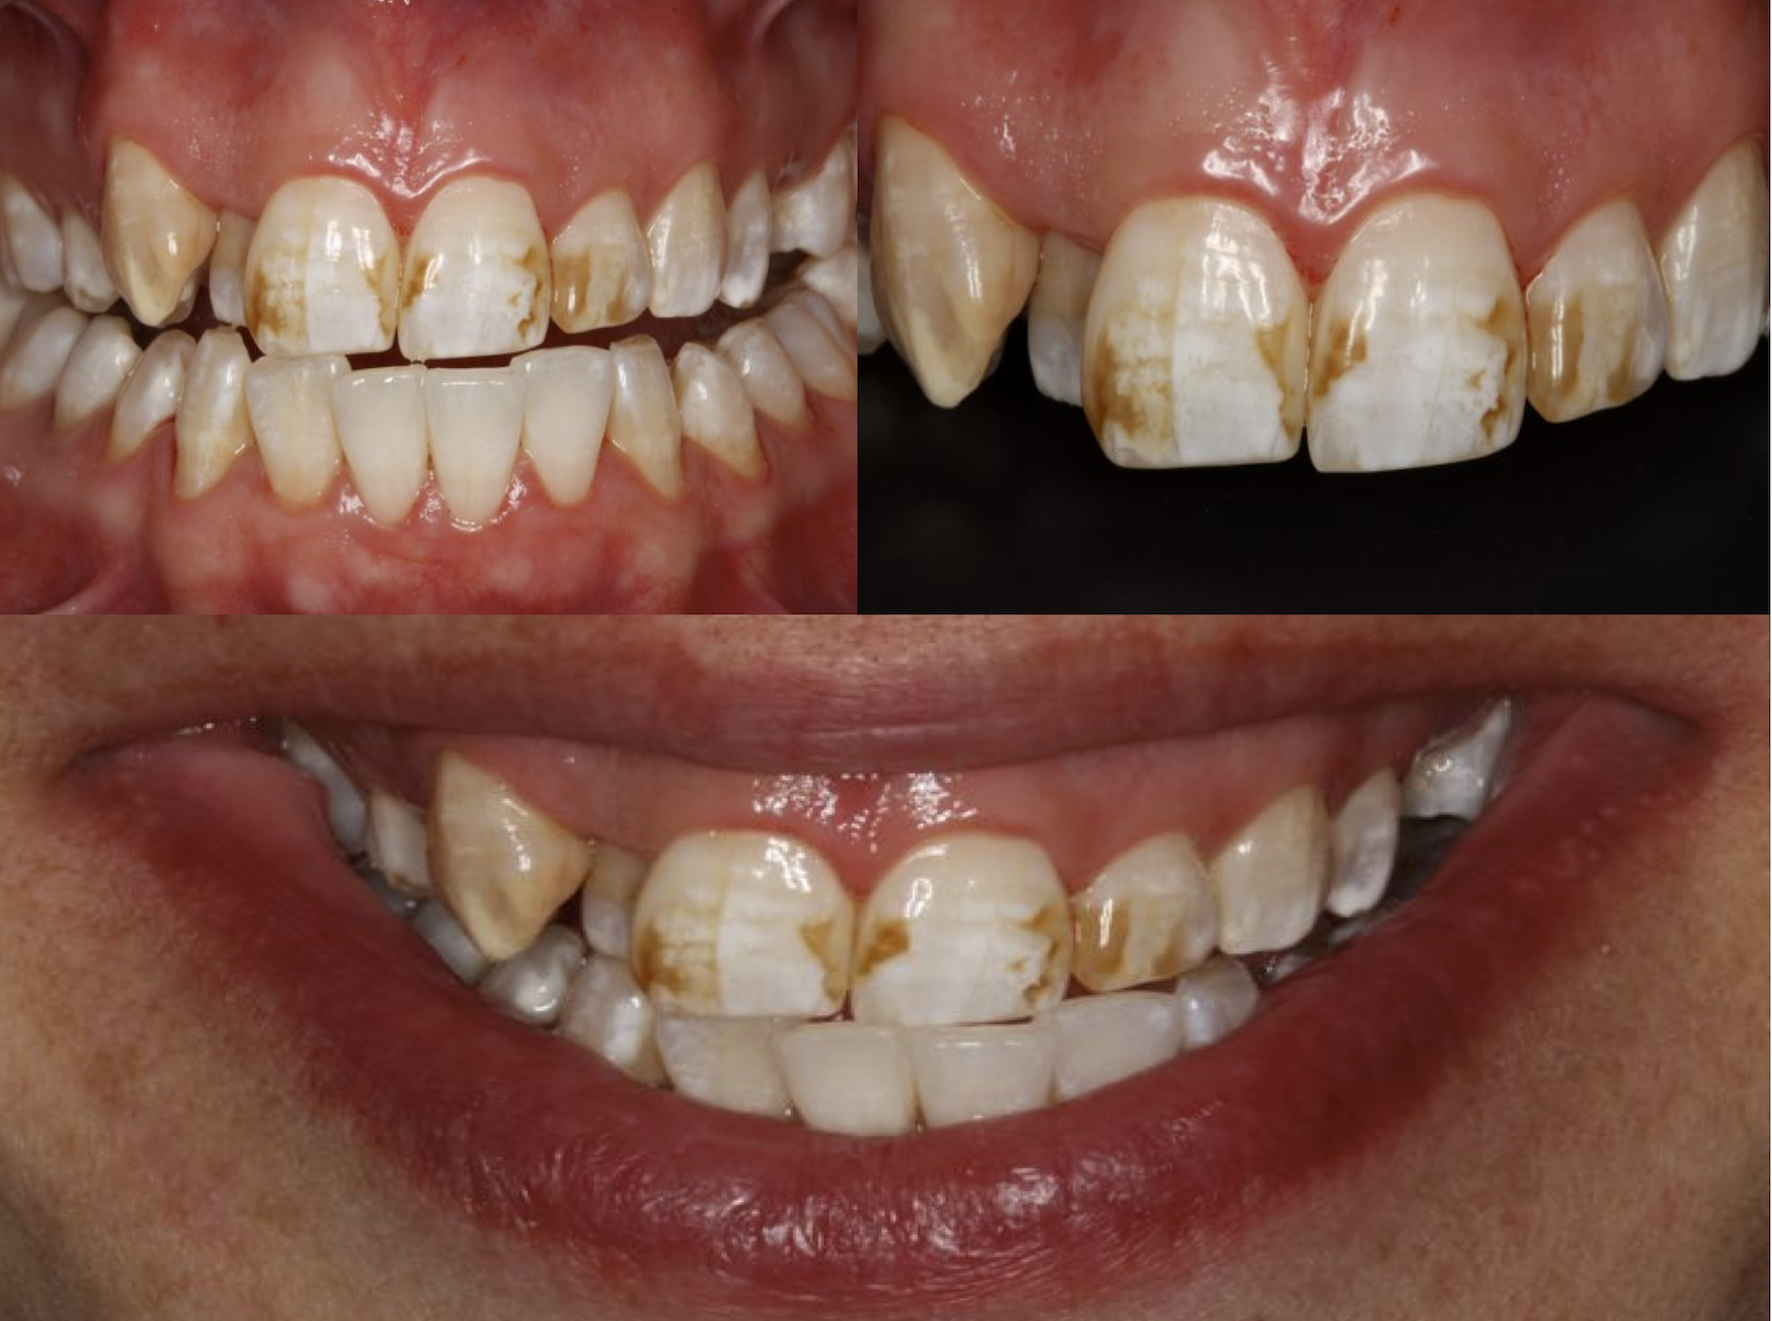

The generalized presence of stain, particularly on anterior teeth, provides an unaesthetic appearance with a negative impact on the patient. The aim of this paper is to report a case of severe chromatic alterations treated with enamel microabrasion associated with infiltration of low-viscosity resin. The intense brownish pigmentation and white spots of fluorosis lose their whitish appearance and look similar to sound enamel. This association of techniques, which might be an alternative to white-masking of intense pigmentation, showed optimal aesthetic results.